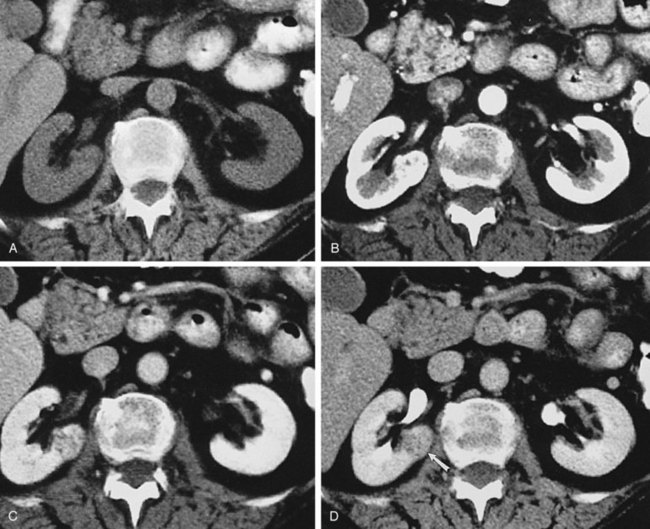

Some patients are not favorable candidates for renal ultrasonography. Obesity, intestinal gas, and physical deformity may be impediments to complete renal evaluation. Renal ultrasonography has poor sensitivity for renal masses less than 2 cm (Warshauer et al, 1988). There is a lack of specificity for renal tumor type except for angiomyolipoma. Angiomyolipoma has characteristics that are distinctive on ultrasonography (highly echoic), but some small renal cell carcinomas have been shown to be indistinguishable from angiomyolipoma by ultrasound criteria (Yamashita et al, 1992; Forman et al, 1993).

Transabdominal pelvic ultrasonography is a tremendously versatile tool for the urologist. It is a noninvasive method for evaluating the lower urinary tract and prostate in men and the bladder in women. A curved array transducer of 3.5 to 5 MHz is most commonly employed to perform transabdominal ultrasonography. In pediatric patients a higher-frequency transducer may be used. In cases where only a residual urine or bladder volume is to be determined, an automated bladder scanner is often employed.

Bladder ultrasonography is most commonly performed with the patient supine and the sonographer on the patient’s right side. The scan should be performed in a warm room, and the patient draped to provide for comfort and privacy. If necessary, a roll may be placed beneath the patient’s hips. Scanning technique depends on the circumstances and the reason for the examination but in general should be performed with a moderately filled bladder. The bladder should be scanned in a sagittal and transverse manner angling the probe into the pelvis so that the bladder can be visualized beneath the pubic bone. Although the prostate cannot be imaged with the same resolution achieved during transrectal scanning, the size and morphology of the prostate can be demonstrated. Although transabdominal scanning is the most common means of evaluating the bladder, the bladder may also be assessed via a transvaginal and transrectal approach. These approaches are useful in patients who are obese or who are not suitable candidates for transabdominal scanning.

Transabdominal pelvic ultrasonography should include evaluation of the lumen of the bladder, as well as bladder wall configuration and thickness. The presence of specific lesions such as stones or tumors should be documented. The structures immediately surrounding the bladder may also be evaluated including the distal ureters, the prostate in men, and the uterus and ovaries in women (Fig. 4–34). The emergence of urine from the ureteral orifices (ureteral jets) can be demonstrated. The clinical value of demonstrating ureteral jets has been questioned. Up to 10 minutes of continuous observation may be required to verify the absence of a ureteral jet (Fig. 4–35) (Delair and Kurzrock, 2006).